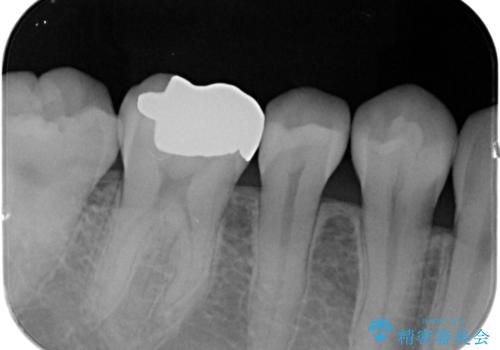

- 過去の樹脂の治療の劣化を治したいとの事で来院。大臼歯の歯は樹脂の範囲が大きくセラミックインレーで処置しても割れてしまう可能性があるため被せ物のご案内をしたところ、なるべく歯を削りたくないとのことでPGAアンレー(ゴールドアンレー)での治療となりました。手前の歯はセラミックの詰め物で治療する事ができました。

- e-maxインレー 7.7万円 PGAアンレー 11万円費用は治療当時の料金となります

歯質の削除量をなるべく最小限にして治療が終わりました。

セラミック、ゴールド共に適合が良く虫歯の再発のリスクが低くなります。